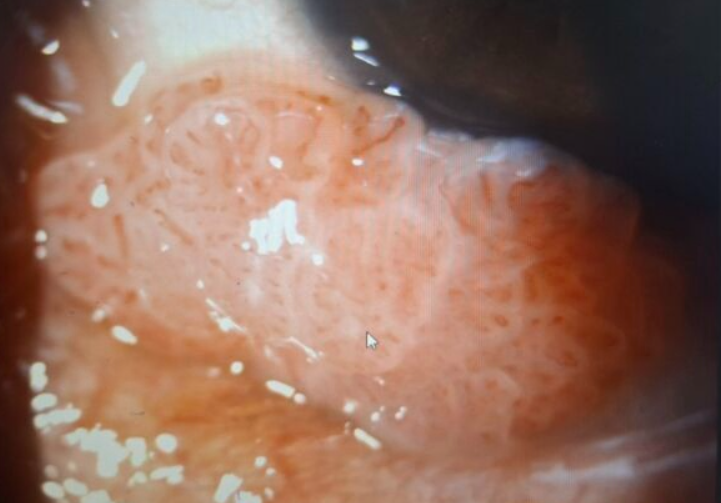

“หูดหงอนไก่ (โรคติดต่อทางเพศสัมพันธ์)” ขึ้นที่ตา 😨

ลักษณะอาการ

- ก้อนนูนคล้ายกุ้งยิง

- ไม่เจ็บ

- โตขึ้นเรื่อย ๆ

- มีลักษณะเป็นติ่งเนื้อ

สุดท้ายต้องรักษาด้วยการจี้และตรวจชิ้นเนื้อ